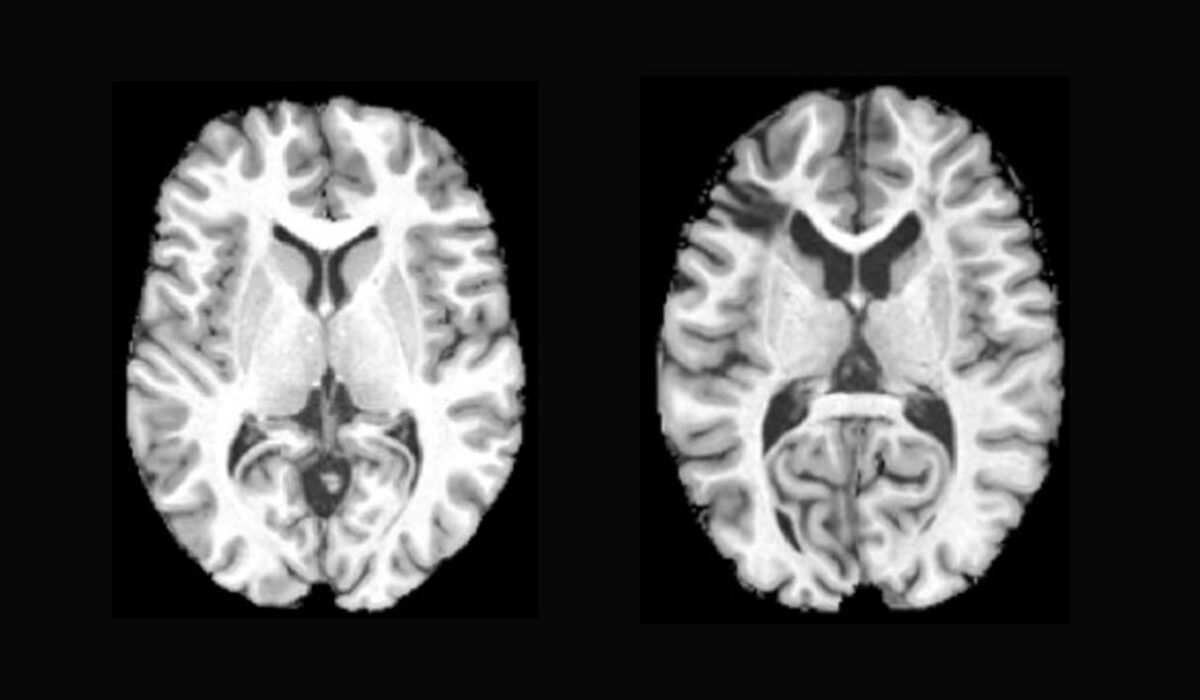

When studying substance use disorders, scientists had thought some of the effects on the brain could stem from use of...